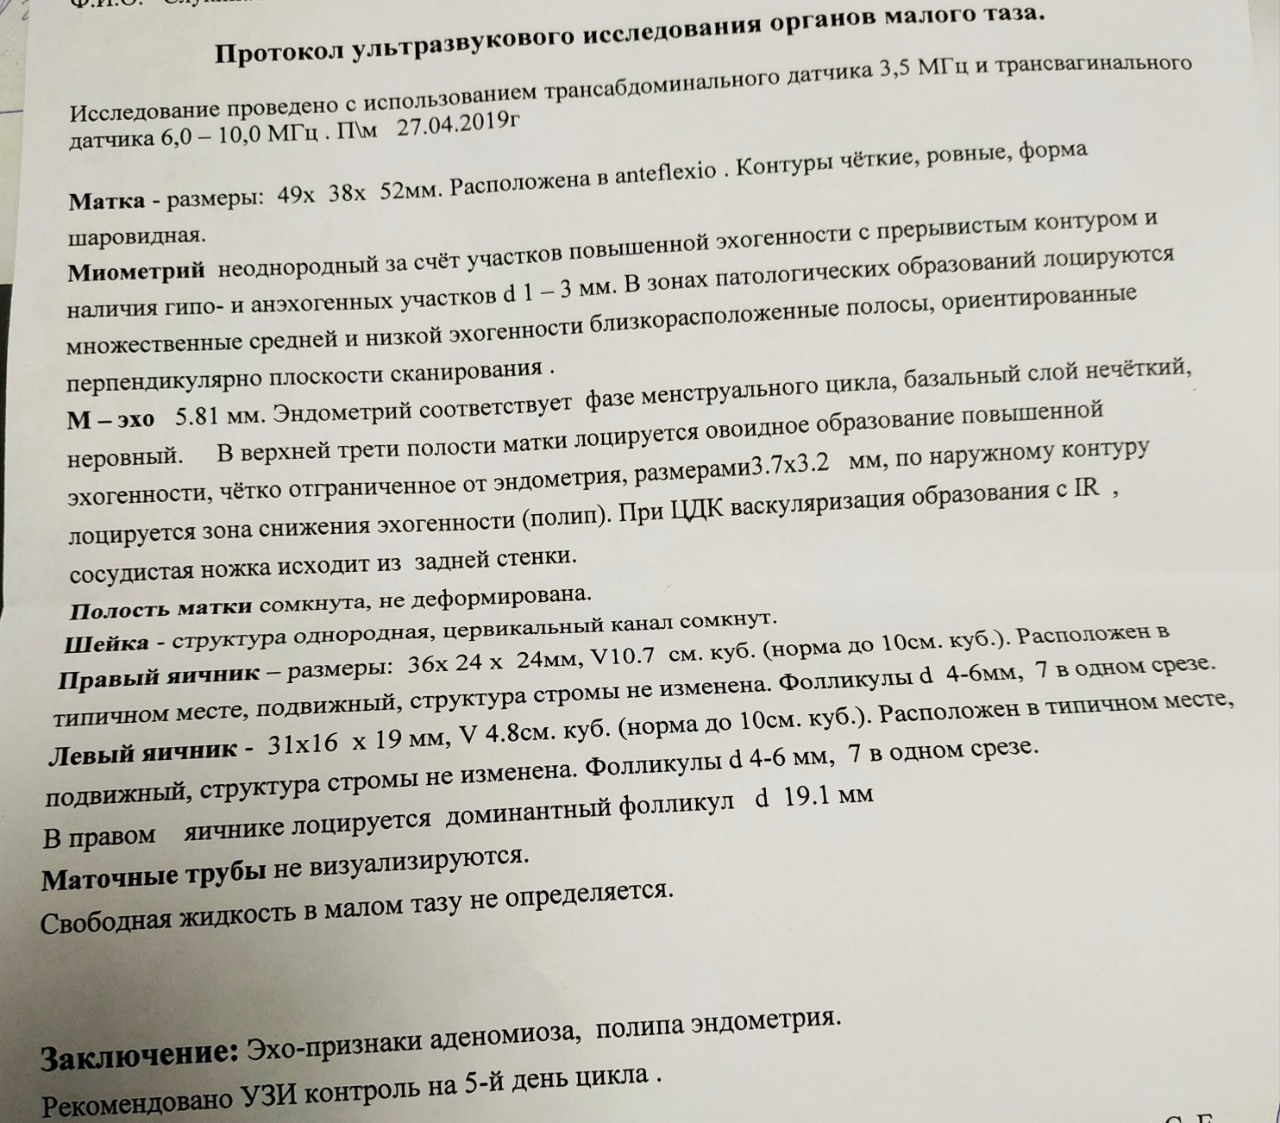

Почему разные заключения на УЗИ?